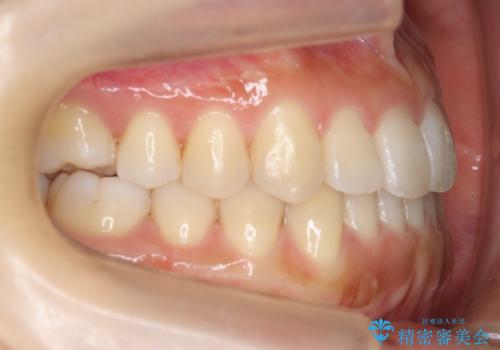

前歯のがたつき インビザラインで 下の奥歯を後ろに下げる

- 上下の前歯のがたつきを主訴に来院。

骨格的に受け口の傾向があり、下の奥歯が前方にに位置しており、下の前歯が特にがたつきが大きい状態でした。

下の奥歯を後ろに下げて下の前歯が前方に出ないように治療しました。